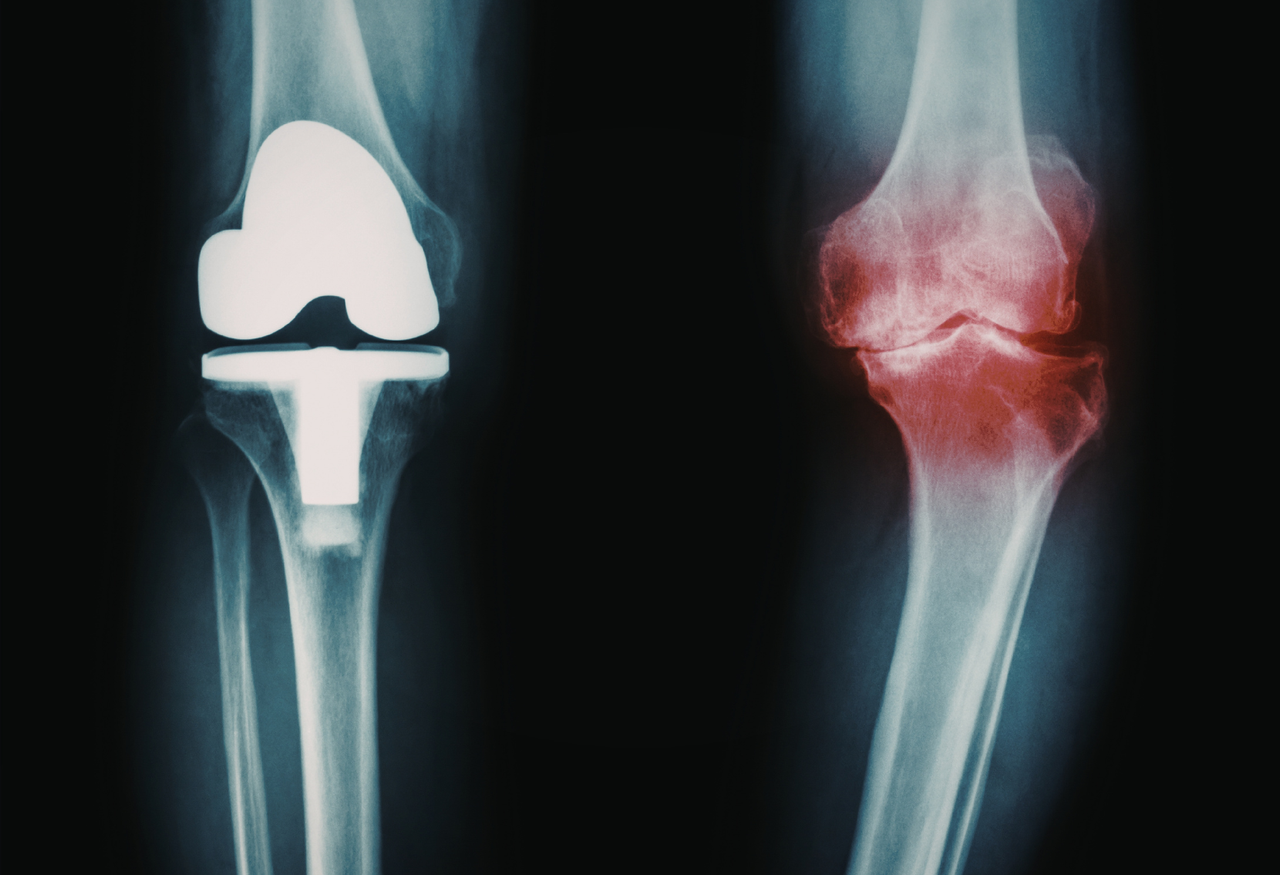

Artrosis_y_desgaste_articular

Artrosis y desgaste articular

Control y manejo del deterioro progresivo de las articulaciones.

✅ Cirugía de fracturas y prótesis articulares.

Cirugía de fracturas y prótesis articulares.

Procedimientos quirúrgicos destinados a estabilizar y reparar fracturas complejas, así como a reemplazar articulaciones dañadas mediante implantes internos, con el objetivo de aliviar el dolor, restaurar la función y mejorar la movilidad del paciente.